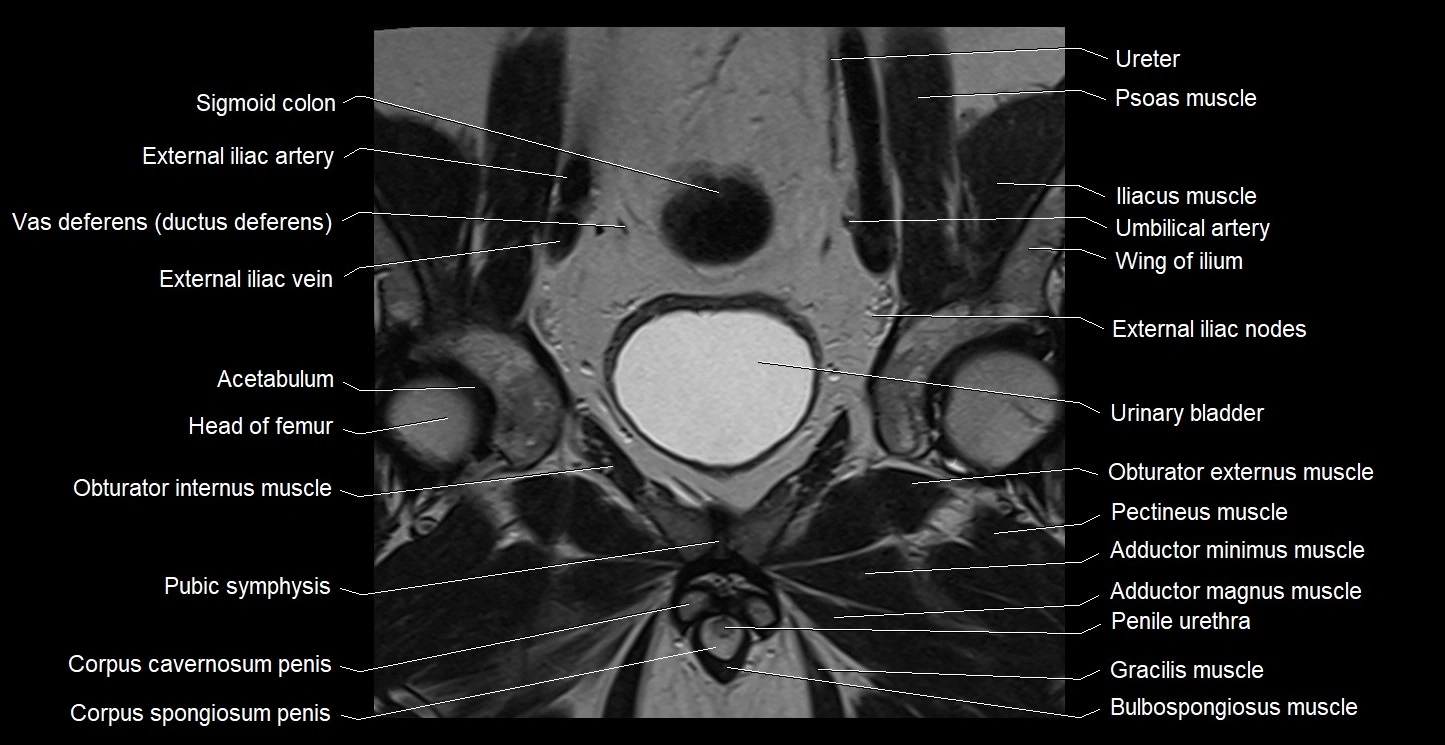

- Acetabulum

- Adductor brevis muscle

- Adductor longus muscle

- Adductor magnus muscle

- Adductor minimus muscle

- Corpus cavernosum

- Corpus spongiosum

- External iliac vein

- Gracilis muscle

- Head of femur

- Obturator externus muscle

- Obturator internus muscle

- Obturator nerve

- Pectineus muscle

- Penile urethra

- Pubic symphysis

- Sigmoid colon

- Urinary bladder

- Vas deferens